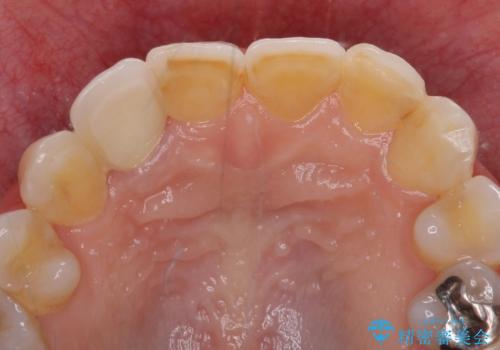

- 前歯のクラウン周りに歯肉が腫れていることを気にして来院された患者様です。

元々磨き残しによる歯肉の腫脹がありましたが、クラウンが歯肉深くに装着されていたため、特に腫脹が目立っていました。

仮歯に置き換えた際に歯周外科処置を行い、歯肉の腫脹が落ち着いたことを確認してオールセラミッククラウンにて補綴することとしました。